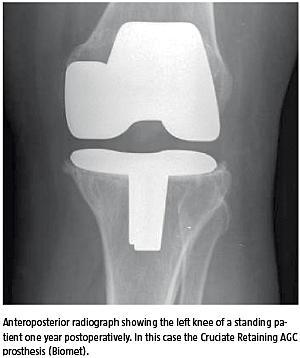

Billede